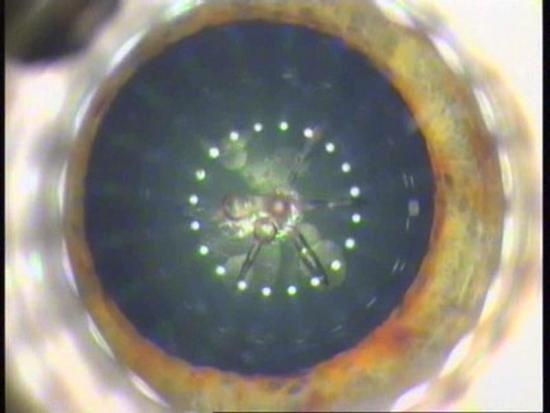

Using an ultrafast laser for lens fragmentation provides better cutting precision and improves the geometric accuracy of the procedure. Credit: Technolas PV.